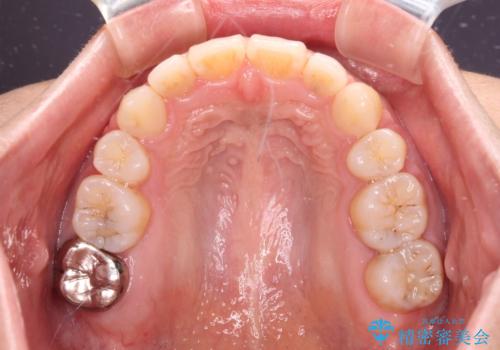

骨格的に下顎がやや前方にあるため、横顔のシルエットが著しく変化することはありませんでしたが、口元はスッキリと引っ込み、唇が閉じやすくなりました。